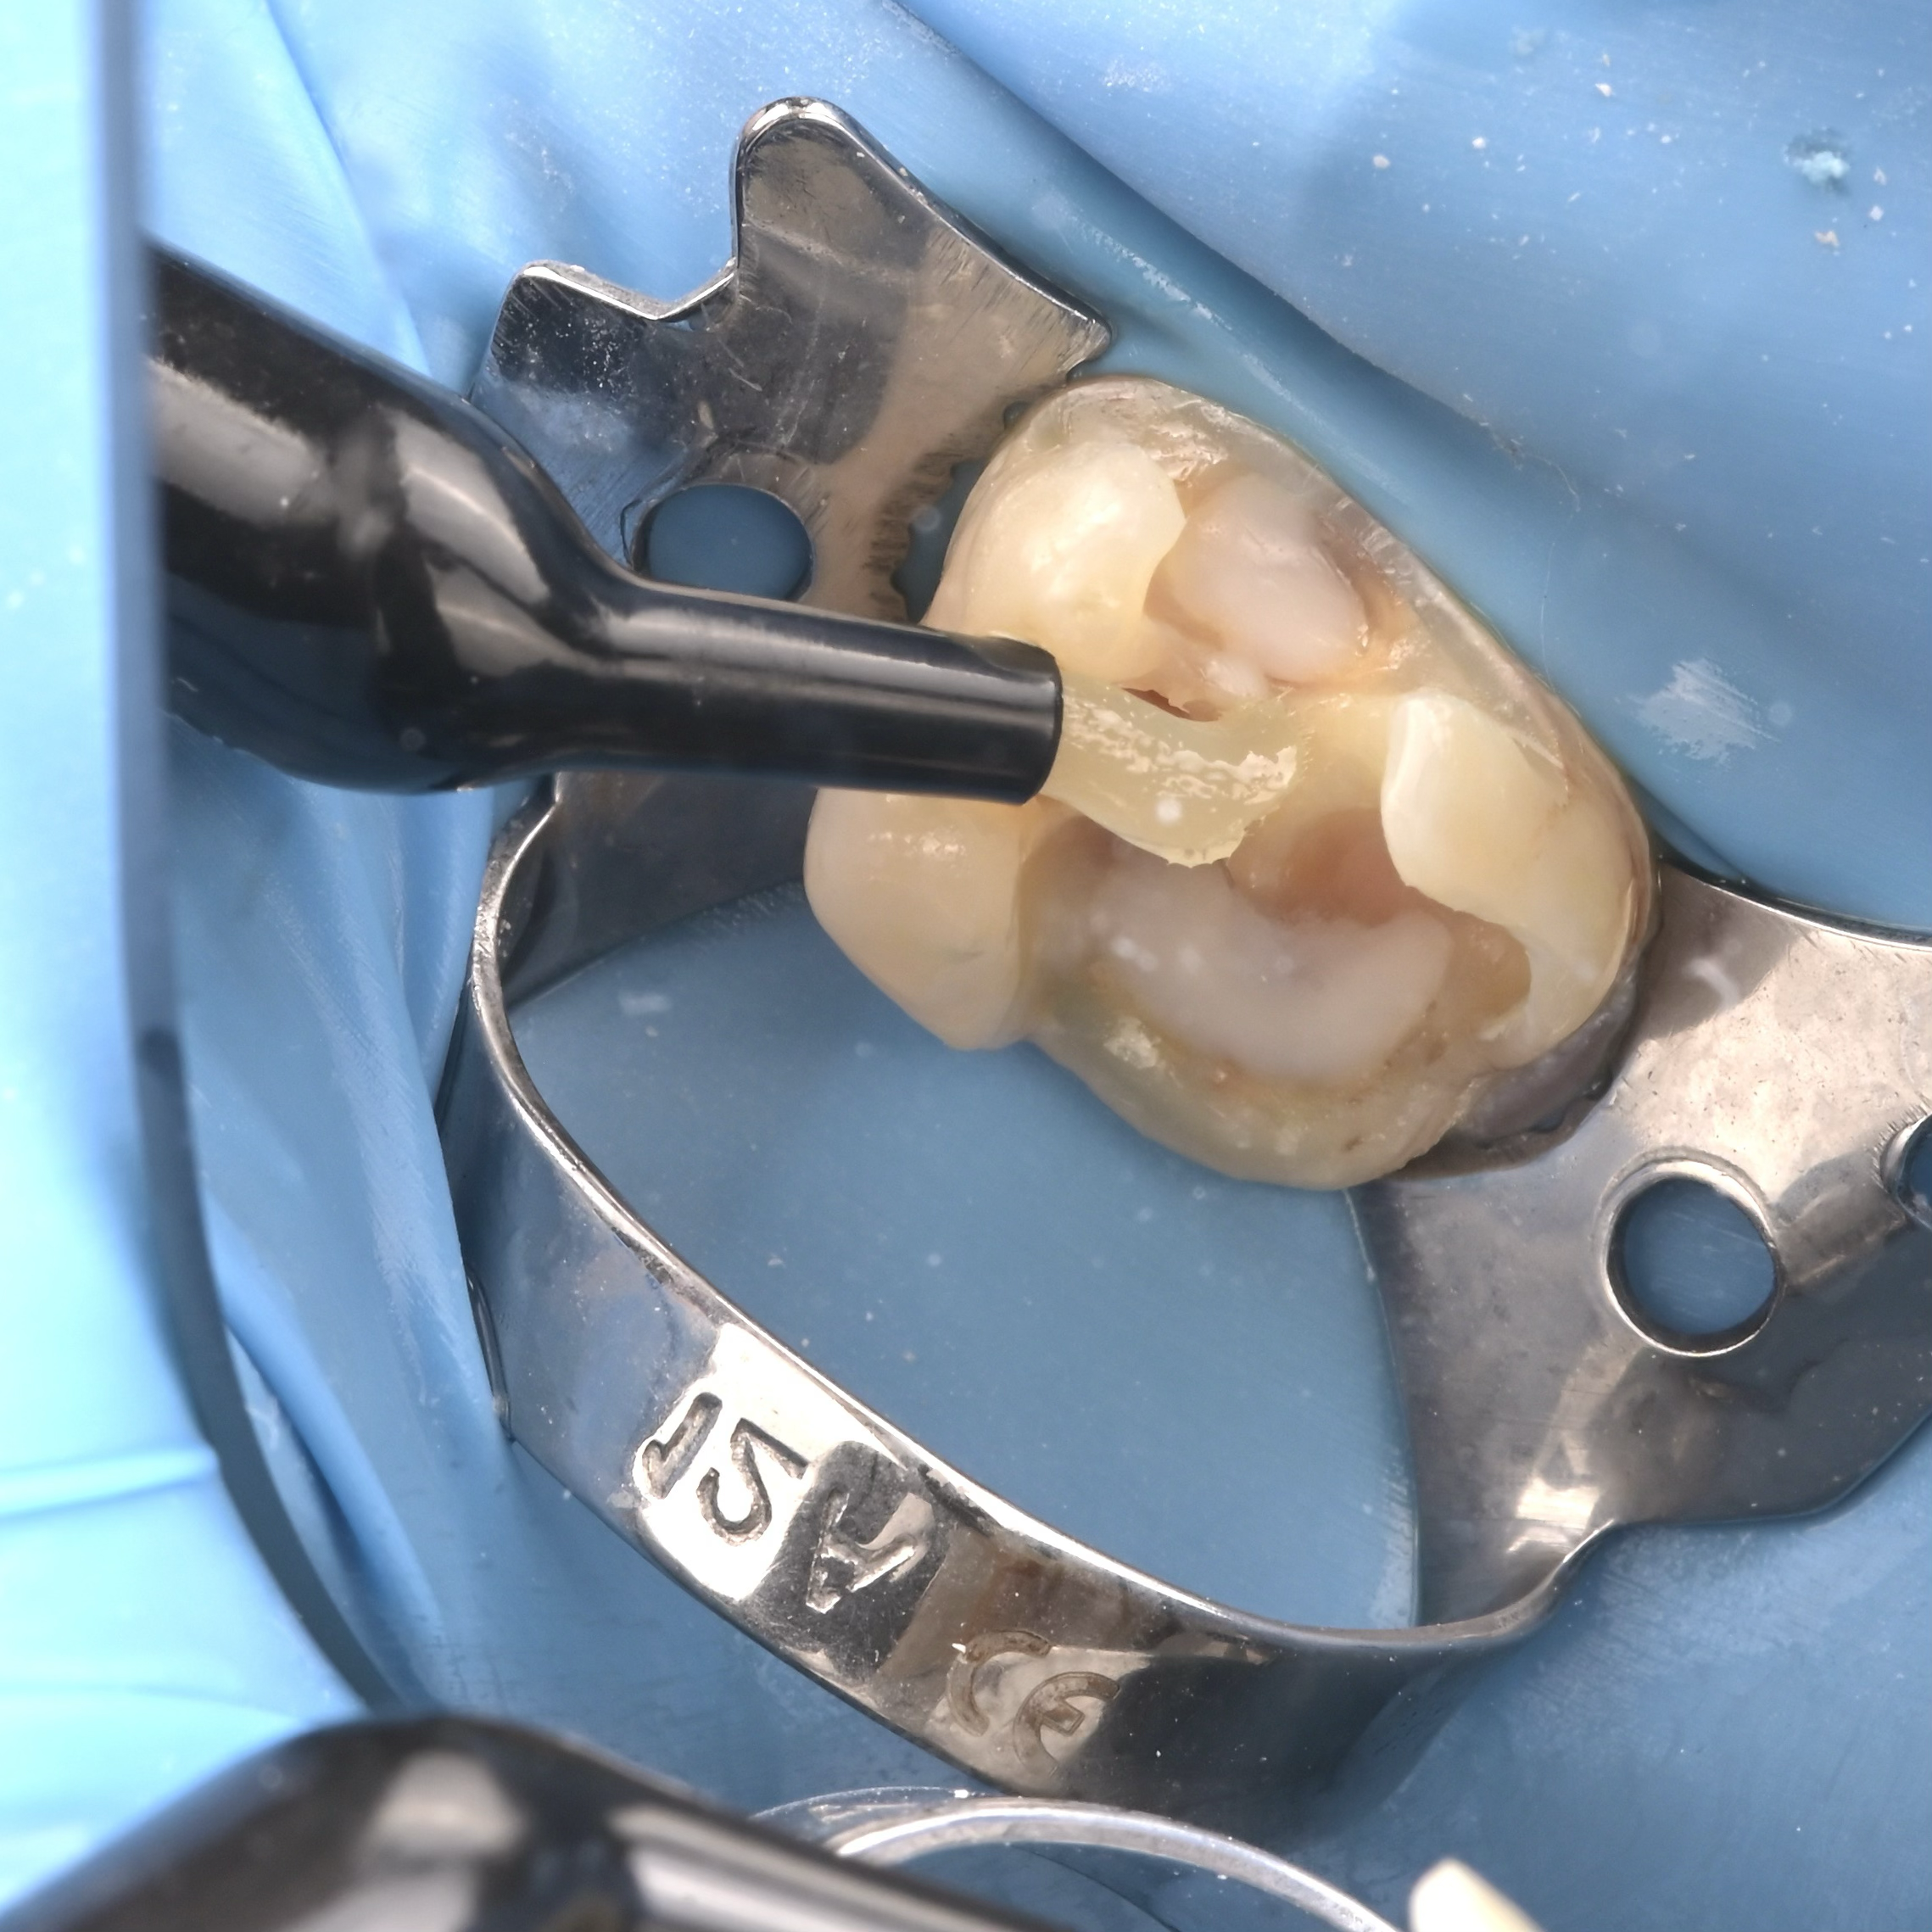

A biomimetikus fogászat egy modern megközelítés, melynek célja, hogy a fogak helyreállítását a fogorvos a természetes fog szerkezetét utánozva végezze el. A módszer kulcsa, hogy a fogat a lehető legkevésbé invazív módon kezelje, maximalizálva a megmaradt egészséges fogszövetet.

Ennek eléréséhez speciális ragasztási technikákat és bio-kompatibilis, üvegszál-erősítésű anyagokat használnak, melyek szorosan kötődnek a foghoz.

A hagyományos koronázással szemben, ahol sok ép foganyagot kell eltávolítani, a biomimetikus eljárásnál csak a sérült részeket távolítják el.

– A betétek (inlay/onlay) olyan nagy kiterjedésű fogtömések, amelyeket a fogtechnikus készít el (a fogon kívül), és speciális ragasztóval rögzít a foghoz, ezzel erősítve meg a megmaradt fogfalat.